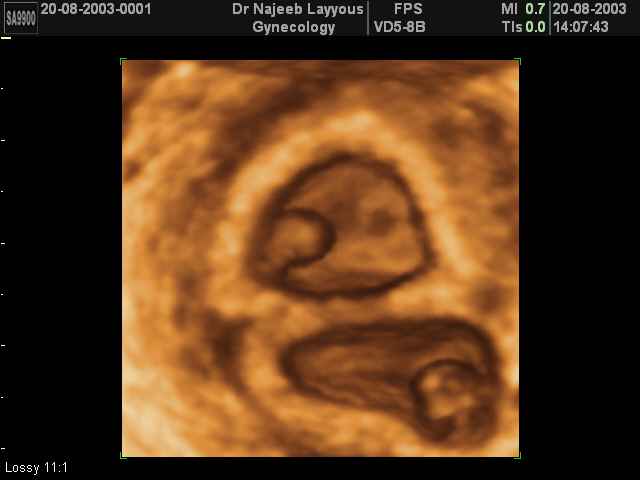

- لقطات فيديو للجنين بجهاز الموجات فوق صوتية رباعي الأبعاد

- صور للجنين في المراحل الأولى من الحمل

- صور لتوائم

صور لتوائم بجهاز الالتراساوند ثلاثي الأبعاد | الدكتور نجيب ليوس